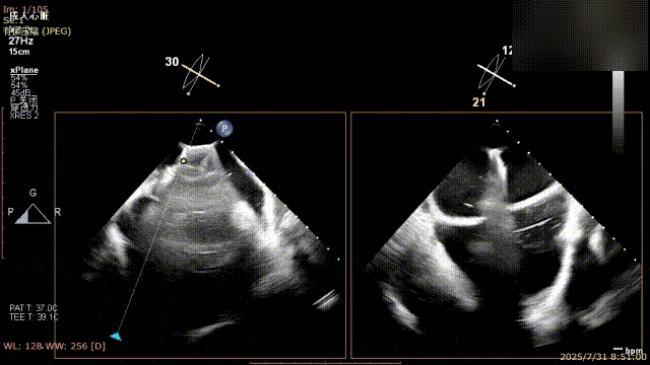

术前完善经食管超声评估,提示该患者双房大,二尖瓣重度反流4+伴后叶脱垂、后叶部分腱索断裂。根据评估结果,心脏大血管外科王安彪主任团队制定了周密的手术方案:植入一枚夹合器,钳夹P1区反流最大处,尽可能夹持全部后叶脱垂瓣叶组织,后续根据术中实时残余分流和跨瓣压差等指标,并依据实时超声监测调整治疗策略。

三维评估

二尖瓣P1脱垂偏心性返流术前影像